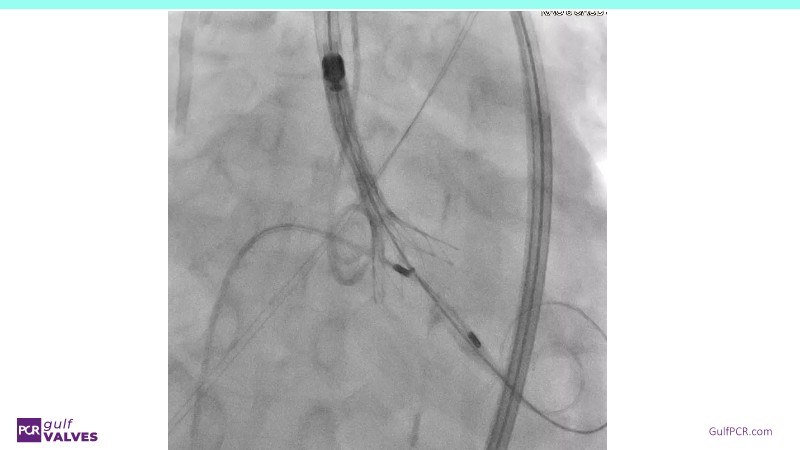

Discover a selection of cases showcasing the key features of the Navitor Valve System and its clinical applications. This session explores auxiliary access, the use of Navitor in alternative access and complex PCI, its performance in challenging peripheral anatomies, and innovative outcomes with the Vantage 30D system.